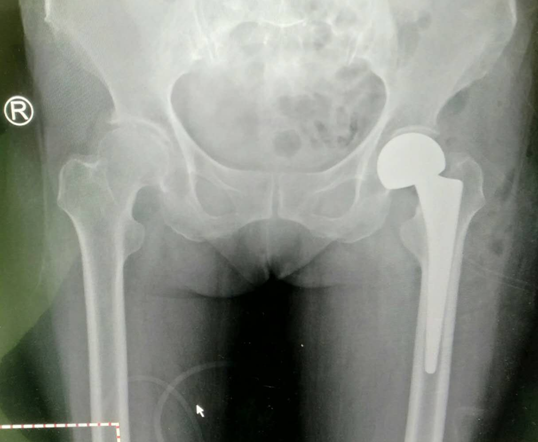

术前片

在给老人做手术前,关节科联合麻醉科进行了详细的术前讨论。老人左侧股骨颈头下型骨折,断端错位,远期股骨头坏死率大,股骨头置换指征明确;术中采取全麻;需要注意保护周围血管神经,安放假体时保持前倾角;股骨头置换后尽早让老人下床活动,注意预防下肢血栓形成,避免长期卧床并发症。